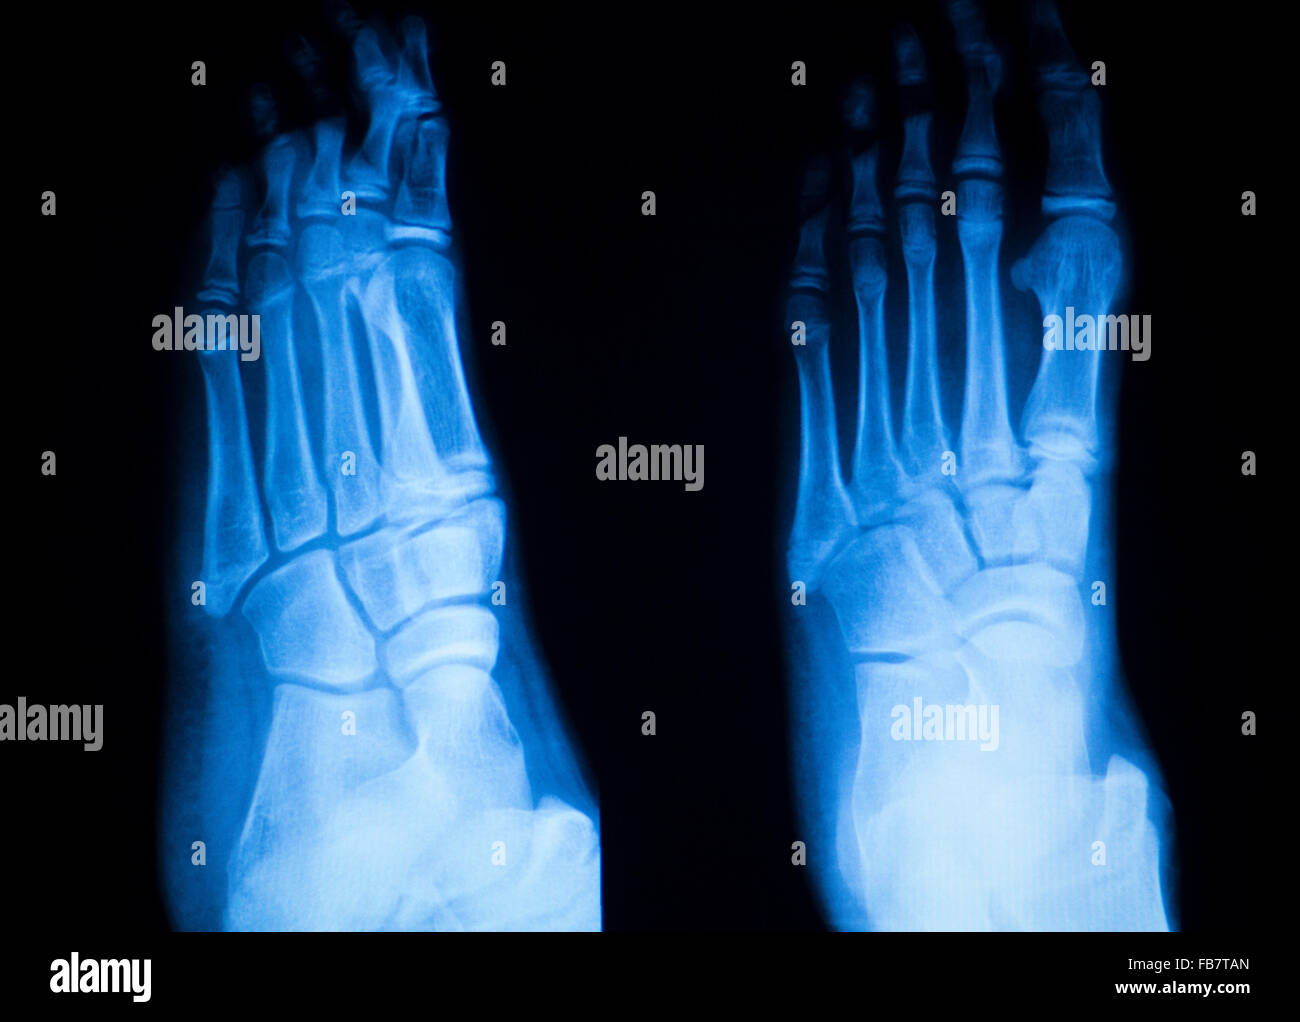

From www.alamy.com

Foot and toes injury xray scan orthopedics and Traumatology radiology Foot Anatomy Radiology Ct December 2, 2005 | journal of clinical ultrasound,. normal ct (with labels) the labeled structures are (excluding the correct side): an ankle and foot computed tomography (ct) may detect the following(7): ultrasonography of capsular morphology in normal and traumatic ankle joints. explore the normal anatomy of the foot and ankle through ct scanning with the american. Foot Anatomy Radiology Ct.